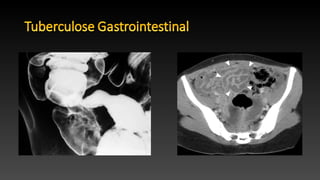

• O abdômen é o foco mais comum de tuberculose extrapulmonar,

com as vísceras sólidas sendo afetadas com maior freqüência.

• TC é o principal método para investigar tuberculose abdominal.

• O conhecimento de exames baritados, como enema, é importante

para evitar erros de diagnóstico nos casos em que a tuberculose não

é inicialmente suspeita.

• Raro, quase sempre envolve a região ileocecal ( 90 % dos casos ),

geralmente , tanto o íleo terminal e o ceco.

• O achado comum na TC é o espessamento mural , que é tipicamente

concêntrico, mas se excêntrico tende a envolver a parede cecal

medial.

• Linfadenopatia localizadas são geralmente observadas.

• Em estudos com bário, a primeira manifestação é espasmo e

hipermobilidade com edema da válvula.

• O espessamento de uma válvula ileocecal incompetente foi descrito

como sendo característica de tuberculose.